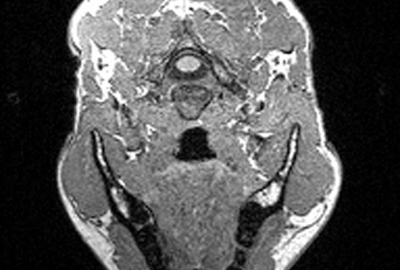

- Muscle-based facial animation considering fat layer structure captured by MRI

Muscle-based facial animation [Lee et al. 1995] is one of the best approaches to realize facial expressions of characters. However, this approach does not consider the personal variation in facial tissue model such as skin thickness. So personal character in emotional expression can not be reflected in this model.